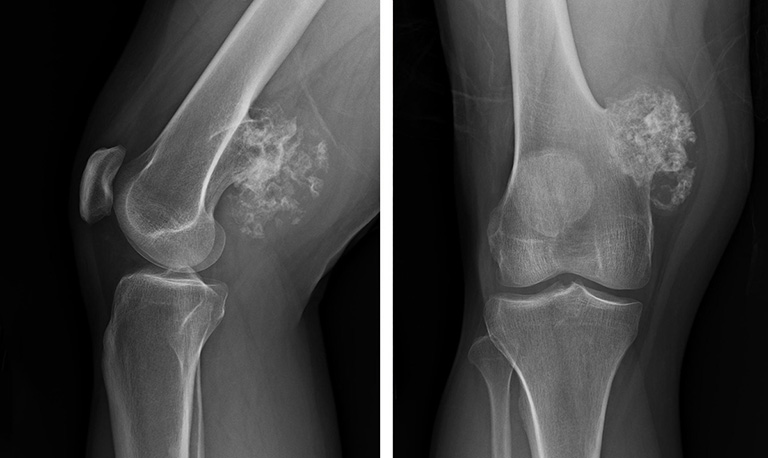

U xương là bệnh gì? Những điều bạn không thể bỏ qua về u…

U xương là bệnh gì? Và đâu là những dấu hiệu nhận biết và cách điều trị hiệu quả căn bệnh này? Bạn muốn hiểu rõ hơn về bệnh u xương? Bài viết này Hukaki sẽ giúp bạn giải đáp mọi thắc mắc về căn bệnh này